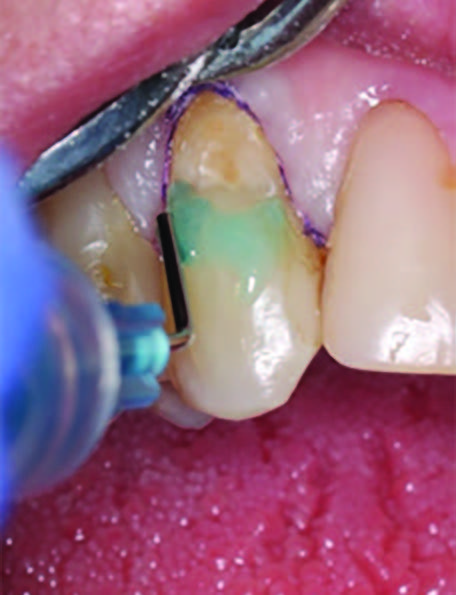

To improve isolation and soft tissue access, a retraction cord was placed before initiating the procedure (Fig. 2). The tooth was evaluated using a caries indicator dye (Kuraray Noritake Dental), helping to identify any remaining infected tissue beneath the dislodged composite (Fig. 3). Decay removal was completed with a diamond bur, and the enamel was bevelled using a starburst pattern to enhance aesthetic blending (Fig. 4). This preparation design was chosen for visual integration rather than bond strength enhancement.

Figure 4. Preparation of the lesion is completed with diamond bur and starburst beveling pattern to enhance aesthetic blending.